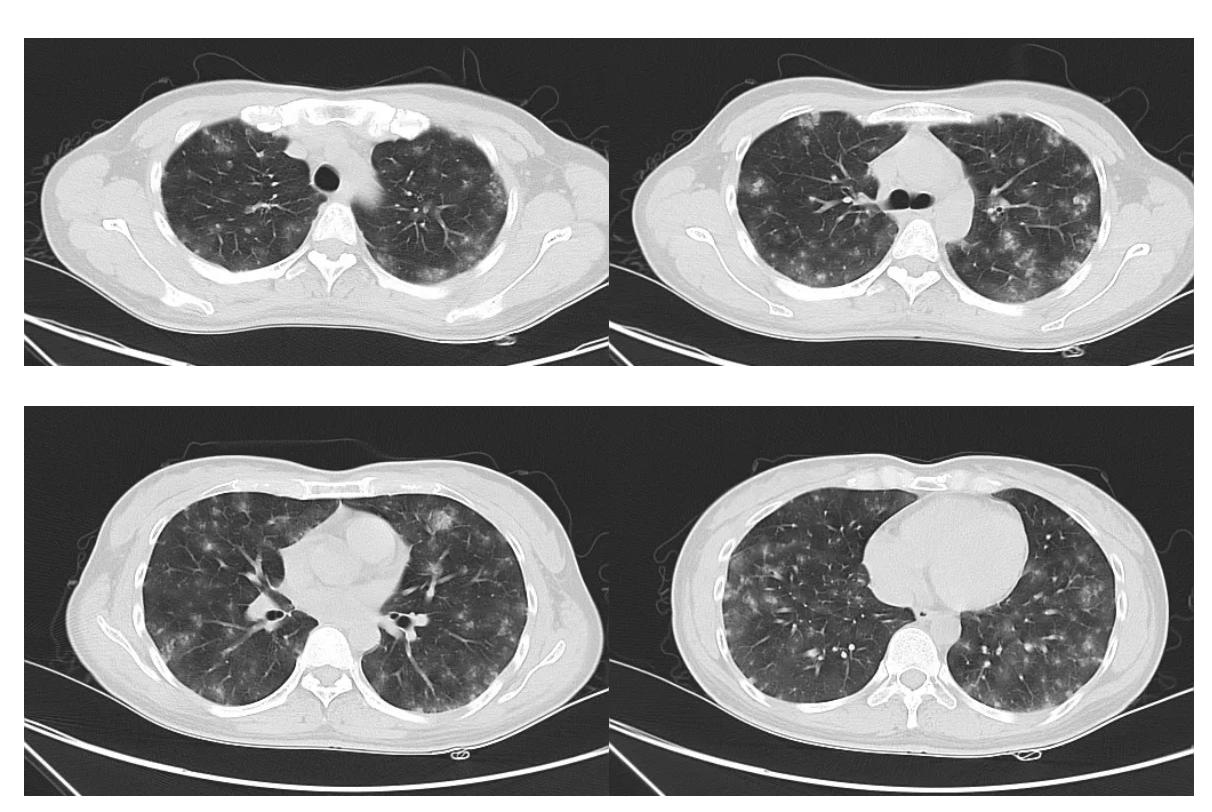

复查胸部CT:

黄国鑫主任(影像科)点评:

患者第一次胸部CT提示双肺多发亚实性结节,分布特点为随机分布,具体表现沿血道分布,无淋巴道及叶间胸膜分布,为中央致密、外周磨玻璃、边界模糊的结节,无肺门淋巴结肿大。患者第二次胸部CT为5天后,可见双肺随机分布结节明显增多、范围增大,散在磨玻璃渗出,以双下肺背侧为主伴部分节段性实变,磨玻璃影明显扩大,结合临床患者咯血逐渐加重,考虑基础疾病考虑感染性及非感染疾病。感染性疾病从影像角度分析,主要考虑侵袭性真菌感染,但患者双肺结节表现为不同阶段,双下肺结节比较致密,且存在胸膜下小结节,随着病情进展,双下肺较致密结节及胸膜下小结节无明显改变,但双中上肺亚实性周围磨玻璃的结节明显增大,这种不同阶段结节从影像学上不太支持真菌感染。从患者沿血管分布病变分析,首先考虑肉芽肿性血管炎,支持点有沿血管分布、多发小结节、肉芽肿性改变;另外病变沿血道播散需注意与肿瘤相鉴别。患者第二次胸部CT进展,弥漫性肺泡积血、双下肺坠积性肺炎从影像角度考虑诊断比较明确。